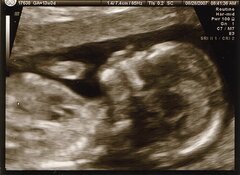

Heidi Crowter est une jeune femme trisomique de 24 ans, au Royaume-Uni. Avec Maire Lea-Wilson, maman d'un petit Aidan également porteur de trisomie 21, elle a décidé d'attaquer la loi britannique sur l'avortement. Cette loi qui autorise, jusqu'à la naissance, l'avortement de foetus porteurs d'handicap, les deux femmes l'estiment profondément discriminatoire envers les personnes atteintes de trisomie 21. Lundi dernier, la Haute Cour de justice (High Court) du Royaume-Uni a accepté de se prononcer sur le recours. C'est une première victoire pour Heidi et Maire, et leurs avocats.

En 2019, 3.183 avortements furent rapportés pour raison de handicap en Angleterre et au Pays de Galles. 656 concernaient des foetus porteurs de trisomie 21. Le Comité des droits des personnes handicapées de l'ONU a fortement critiqué les pays qui autorisaient l'avortement sur base du handicap, recommandant au Royaume-Uni de modifier sa législation de façon à ne pas discriminer les bébés porteurs de handicaps. Interrogée par Channel 5 News sur ce qu'est la vie d'une personne trisomique, Heidi Crowter répond spontanément : « Je dirais que c'est plein d'aventure, et une vie d'opportunités. Et je dirais : regardez les personnes derrière ce chromosome supplémentaire, et voyez leur beauté intérieure ». Heidi dénonce clairement la discrimination dont ses semblables sont victimes : « Un bébé normal peut être avorté jusqu'à 24 semaines (ndlr : au Royaume-Uni), mais un bébé avec le syndrome de Down peut être avorté jusqu'à la naissance. Étant moi-même atteinte du syndrome de Down, je trouve cela profondément blessant. Cela me fâche vraiment et me fait pleurer ».